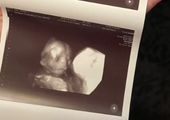

Niesamowite zdjęcia USG. Nawet lekarze byli zaskoczeni

Badanie USG to zwykle jeden z najbardziej wyczekiwanych momentów w czasie ciąży. Jesteśmy ciekawi, jak będzie wyglądać nasze dziecko, jaki będzie miało kształt nosa czy uszu. Czasem jednak zamiast radości, zdjęcie USG może stać się powodem niepokoju i stresu. Tak było w przypadku Jade Boyland z Somerset w południowo-zachodniej Anglii, która na swoim pierwszym badaniu USG ujrzała twarz swojego dziecka. Była przerażona, ponieważ zobaczyła zarys zgarbionego malucha, z wielkimi oczami i wydłużonymi palcami, które przypominały szpony. Jade przyznała, że gdy pierwszy raz zobaczyła twarz swojego malucha, nazwała "demonicznym dzieckiem". Początkowo żartowała z tego, jednak wraz z biegiem ciąży coraz bardziej przejmowała się kwestią wyglądu córki po porodzie. Niepokój jednak okazał się zbyteczny, ponieważ urodziła piękną, zdrową córeczkę, która obecnie ma 9 lat. Po "demonicznym wyglądzie" nie ma żadnego śladu. Jednak, jak twierdzi mama, córka ma "demoniczny charakter" i żartuje, że wiedziała to od pierwszego badania. Tak obecnie wygląda Lydia